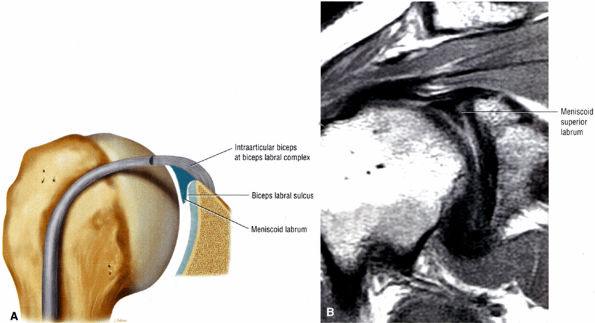

FIGURE 8.77 ● (A) Type 3 BLC with meniscoid superior labrum and a free central margin. (B) Coronal PD FSE image illustrating a large meniscoid superior labrum in a type 3 BLC.